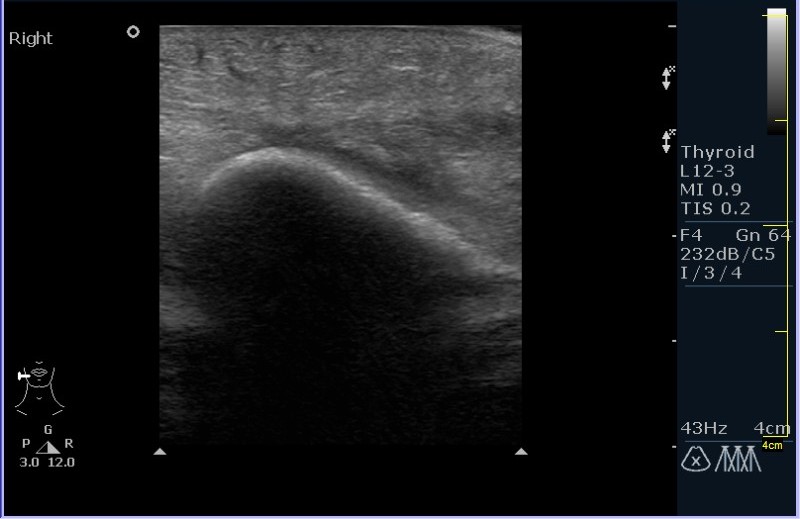

УЗИ области правой околоушной железы и угла нижней челюсти.

Девочка 8 лет, с опухлостью щеки и области правого угла нижней челюсти, резко боезненной при пальпации. В анамнезе (после наводящих вопросов :ugeek: ), визит к стоматологу около месяза назад.